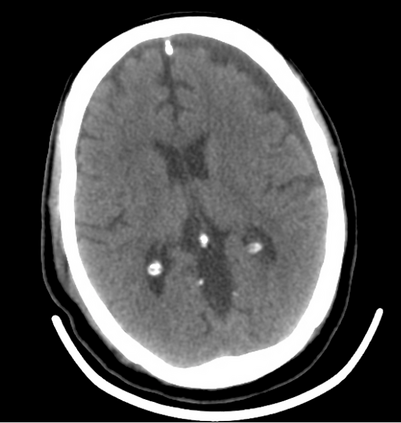

In this study, we aim to initiate the development of Radiology Foundation Model, termed as RadFM.We consider the construction of foundational models from the perspectives of data, model design, and evaluation thoroughly. Our contribution can be concluded as follows: (i), we construct a large-scale Medical Multi-modal Dataset, MedMD, consisting of 16M 2D and 3D medical scans. To the best of our knowledge, this is the first multi-modal dataset containing 3D medical scans. (ii), We propose an architecture that enables visually conditioned generative pre-training, allowing for the integration of text input interleaved with 2D or 3D medical scans to generate response for diverse radiologic tasks. The model was initially pre-trained on MedMD and subsequently domain-specific fine-tuned on RadMD, a radiologic cleaned version of MedMD, containing 3M radiologic visual-language pairs. (iii), we propose a new evaluation benchmark that comprises five tasks, aiming to comprehensively assess the capability of foundation models in handling practical clinical problems. Our experimental results confirm that RadFM significantly outperforms existing multi-modal foundation models. The codes, data, and model checkpoint will all be made publicly available to promote further research and development in the field.